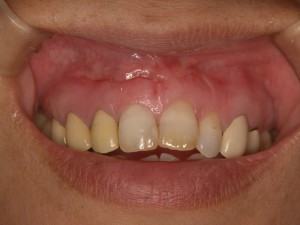

歯肉がこのように。

その当時は、顕微鏡治療のかけ出しのころで、まだまだ歯肉の切開位置ややり方、縫合の仕方が未熟だったのだと思います。

私、一応歯周病専門医でもあるので、歯肉、特に前歯の審美領域であればこのような瘢痕が出来ないように行いたい。笑っても決して見える位置ではないのですが、出来ることなら手術をしたことすら忘れてしまうような傷跡を残さない治療をしたいと常々思っており、その後現在に至るまで研鑽を積んでおります。

なので、歯根の病気を治すために全力を傾ける外科手術であっても、歯肉をいかに扱うかということを考えながら現在手術を行っています。

手術直後の縫合時の写真はこちら

そして、術後3ヶ月でセラミックのかぶせ物を装着したところが、クリニックホームページにありますようにコチラ

8年間の進歩はありますでしょうか?